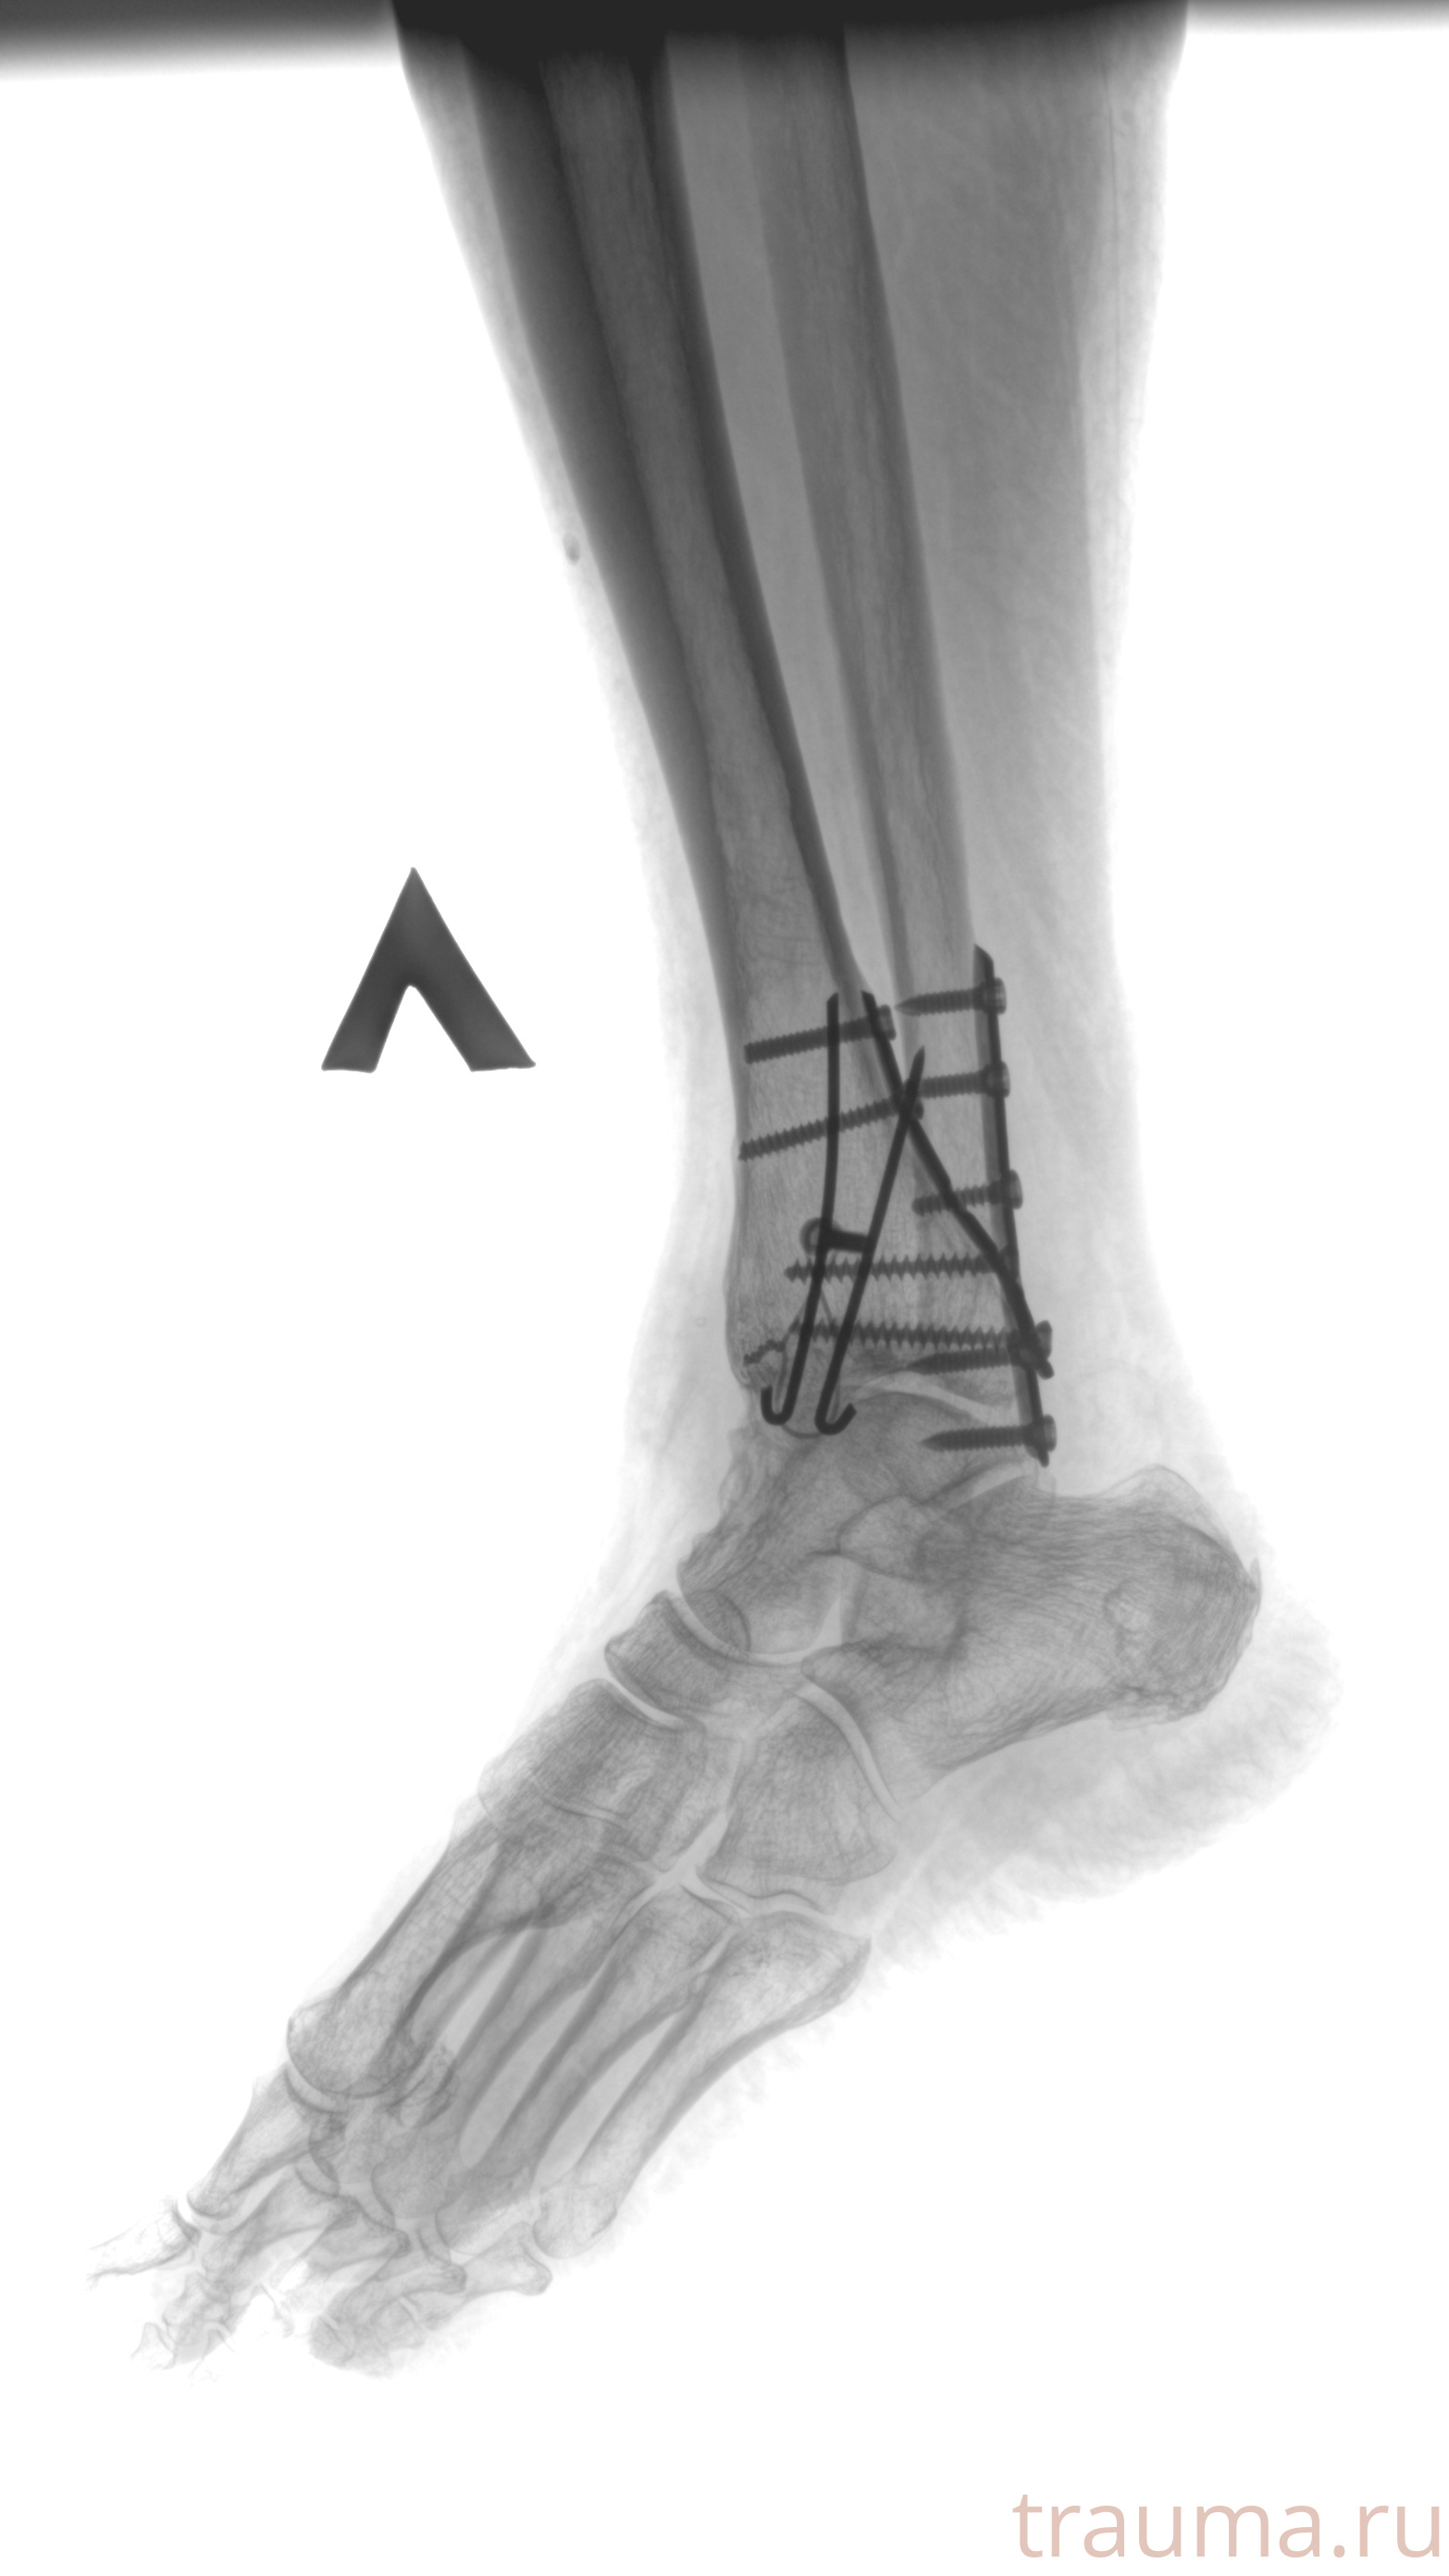

Рентгенограммы